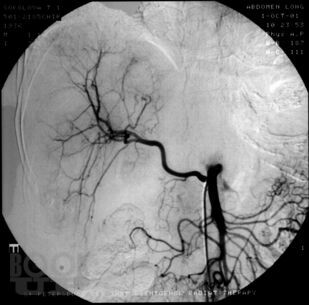

В монографии проанализированы данные литературы и собственные результаты лечения более 700 больных (1983- 2001) первичным и метастатическим раком печени. Дан обзор наиболее часто применяемых рентгеноэндоваскулярных вмешательств. В случае нерезектабельного поражения внутрисосудистая терапия включает регионарную химиоинфузию, эмболизацию, химиоэмболизацию печеночной артерии и воротной вены. Оценены возможности указанных рентгеноэндоваскулярных вмешательств, а также предоперационной механической эмболизации воротной вены при резектабельных опухолях. Рассмотрена роль адъювантной локорегионарной терапии после выполнения резекции печени. Сделано заключение о том, что рентгеноэндоваскулярные вмешательства играют важную роль в лечении злокачественных опухолей печени. Комбинированный подход к лечению злокачественных новообразований печени позволяет расширить возможности оказания помощи больным и добиться улучшения отдаленных результатов.